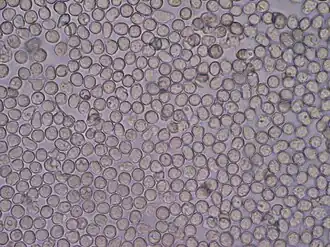

Glóbulos brancos de uma amostra de urina vistos em um microscópio.

1. Leucócitos. A leucocitúria se correlaciona a processos inflamatórios e infecciosos do sistema urinário.

2. Hemácias devem ser avaliadas quanto à quantidade e morfologia (presença ou ausência dismorfismo eritrocitário).

3. Células epiteliais de vários tipos, oriundas da descamação a partir de diversos pontos do trato urinário. Sua morfologia é indicativa de seu local de origem. Sua presença em quantidade elevada é anormal.